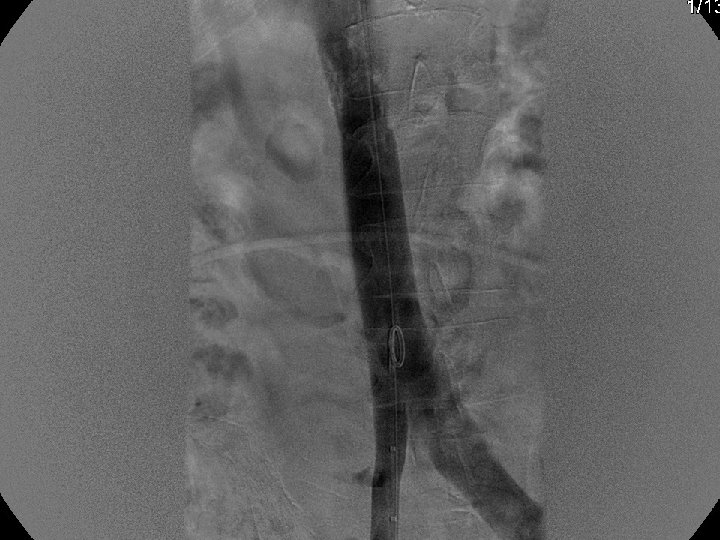

IVC Filter Removal Straight forward and Complex

Removal of an “Intravascular Foreign Body” Straight forward Loop snare Grasping device Complex Multiple devices used including angioplasty balloons, bronchoscopy forceps, and the“in situ” snare technique.

Recovery (G 2) Retrieval

Can a Permanent IVC Filter be Removed?